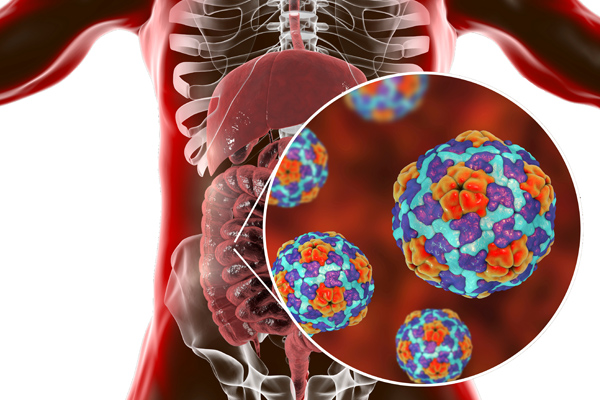

Jon and Laura Green are siblings sharing similar symptoms. Both have a yellow tinge to their skin and the whites of their eyes...